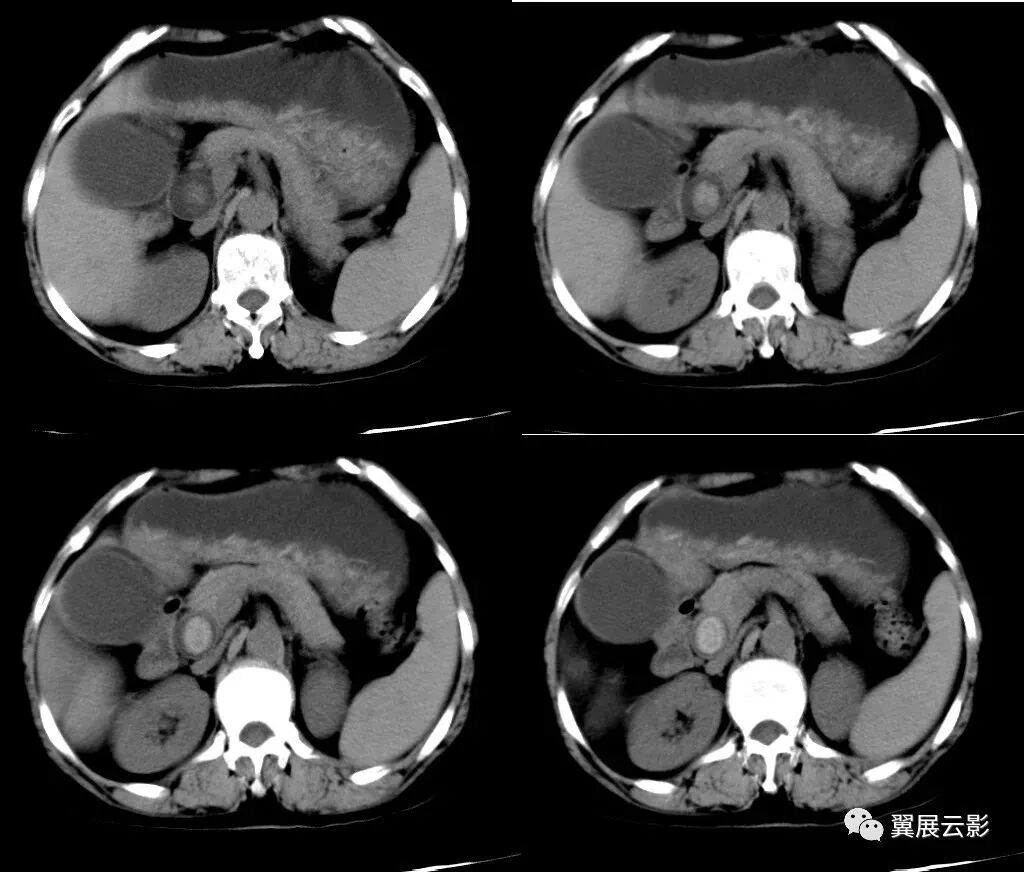

20、棒棒糖征

棒棒糖征见于横断面增强CT或MRI图像上,可见到多个较大的不强化或结节状边缘强化的肿块,肝静脉或门静脉行向这些病灶时逐渐变细并终止于这些病灶边缘,形成类似棒棒糖样的外观。棒棒糖征被认为是肝脏上皮样血管内皮瘤的典型表现。此征可以帮助医师在横断面影像上更好地识别肝脏上皮样血管内皮瘤。棒棒糖征主要包括2个结构:一是在增强片上呈低密度边界清楚的肿块,代表棒棒糖中的糖果;二是在组织学上闭塞的静脉,包括肝静脉和门静脉,代表棒棒糖中的棒子。边界不清楚的肿块、肿块均不符合棒棒糖征的特点。如果病灶中央出现瘢痕样强化或肿块明显或水规则强化,也不能判定为棒棒糖征。强化的静脉应该终止于病灶边缘或仅仅伸到病灶的强化环内,如果血管穿过病灶或被肿块推移,以及形成侧支血管等,均不能考虑棒棒糖征。

肝脏上皮样血管内皮瘤的CT表现主要包括大小不等的多灶性低密度结节,这些结节可以逐渐长大并融合成大的肿块,多分布在肝脏的边缘,增强扫描可见这些结节呈周边环状强化。通常可见到钙化、中心低密度以及包膜内陷。有25%~45.1%的患者观察到有转移,转移部位通常在肺、淋巴结、脾、哥和其他实质性器官。

MRI T1加权像上结节多表现为低信号,T1增强呈边缘强化,正常肝实质强化较肿瘤强化明显,肿瘤中心部分与 CT扫描类似呈低信号。T2加权像肿瘤多表现为不均匀高信号,肿瘤内信号成分较CT更复杂,中心部分信号减低可能与癌内出血、凝固性坏死及钙化有关。

CT(棒棒糖征)

MRI(棒棒糖征)